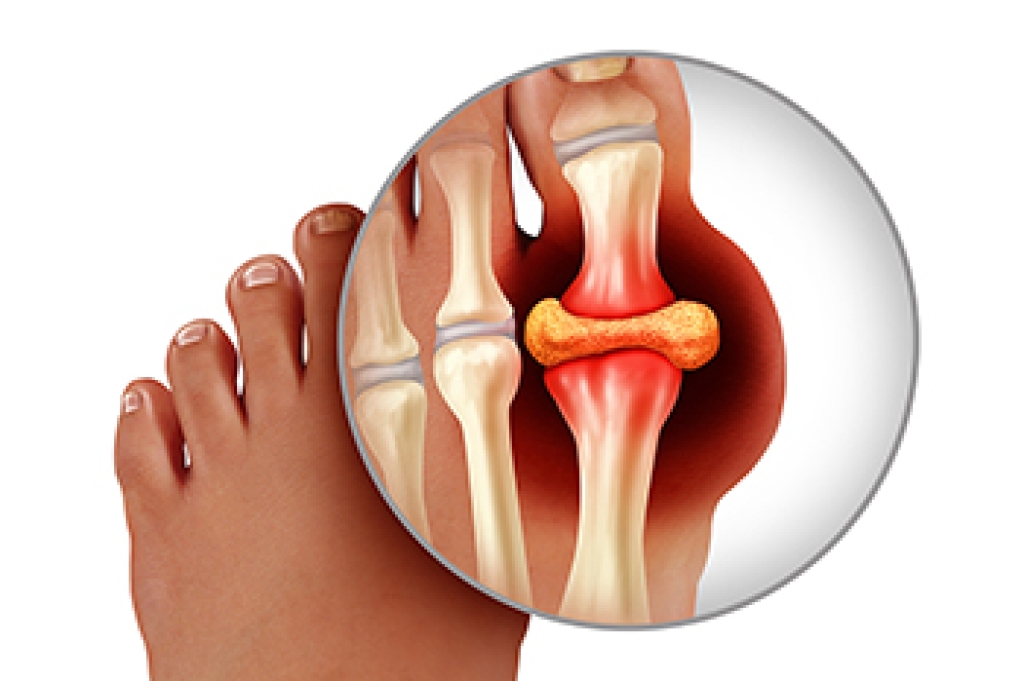

Arthritis is a joint disorder that involves the inflammation of different joints in your body, such as those in your feet. Arthritis is often caused by a degenerative joint disease and causes mild to severe pain in all affected areas. In addition to this, swelling and stiffness in the affected joints can also be a common symptom of arthritis.

In many cases, wearing ill-fitting shoes can worsen the effects and pain of arthritis. Wearing shoes that have a lower heel and extra room can help your feet feel more comfortable. In cases of rheumatoid arthritis, the arch in your foot may become problematic. Buying shoes with proper arch support that contour to your feet can help immensely.